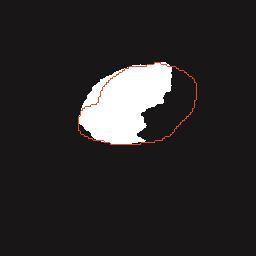

乳腺癌是全球女性最常见的恶性肿瘤之一,准确的病变分割对于乳腺癌的早期诊断与治疗具有重要意义。然而,由于病变形态的多样性以及超声成像机制的复杂性,现有基于深度学习的乳腺超声图像病变分割方法在分割准确性方面仍面临巨大挑战。为进一步提升乳腺超声图像中病变区域的分割精度,该文基于经典U-Net架构,提出了一种新型乳腺超声图像病变分割网络(CWSASKM-BBAM-Net)。首先,在网络中引入逐通道空间自适应选择核卷积模块(CWSASKM),根据不同通道的语义特征为每个空间位置自适应选择感受野大小,以增强多尺度信息的建模能力;然后,引入双向边界感知机制(BBAM),通过融合正向与反向注意力,对目标显著区域及其边界进行协同建模,同时逐步提升对非显著区域与病变区域的区分能力,以进一步强化边界信息的表达;最后,在3组公开乳腺超声图像数据集(BUSI、UDIAT和STU)上开展分割实验。结果表明:该方法在数据集BUSI上的杰卡德指数、精确率、召回率和Dice相似系数分别为71.97%、82.85%、81.40%和80.44%,较次优方法分别提升1.69、1.05、1.28和1.84个百分点;在数据集UDIAT上,这4项指标分别达到78.14%、88.31%、86.73%和86.10%,较次优方法分别提升了2.75、2.04、0.56和2.01个百分点;在外部数据集STU上,该方法也取得了优于其他方法的整体表现。实验结果表明,CWSASKM-BBAM-Net在乳腺超声图像分割任务中展现出更优的整体性能。